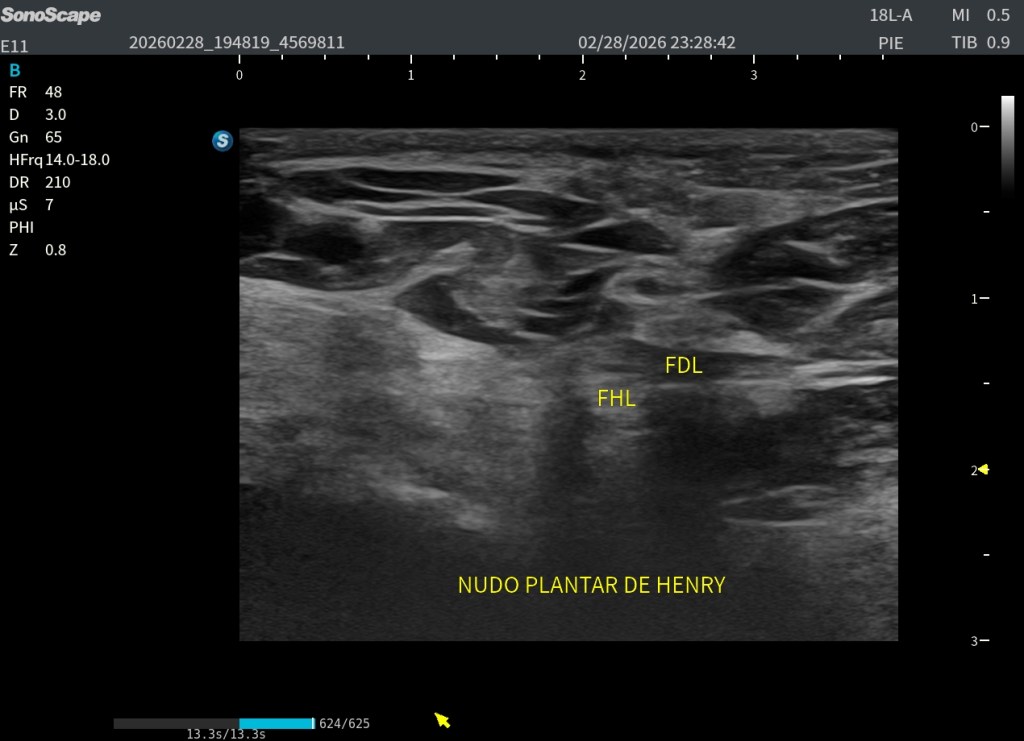

En la porción profunda y medial de la planta del pie se produce un punto anatómico clave: ambos tendones se cruzan. Este cruce es lo que se conoce como nudo plantar de Henry. Es fundamental comprender que este entrecruzamiento ocurre en un plano profundo y que ambos tendones llegan a esa zona desde la región interna del tobillo.

Existe un detalle anatómico determinante que debemos tener muy claro: en el punto exacto del cruce, el FHL es profundo al FDL. Es decir, el tendón del primer dedo queda situado por debajo del tendón de los dedos largos. Esta relación espacial es constante y resulta esencial para la correcta interpretación ecográfica.

En esta localización exacta se demuestra de forma precisa el cruce de ambos tendones, que corresponde al nudo plantar de Henry. Justo debajo, en la imagen situada bajo este texto, se representa la misma región tanto en ecografía como en su correlación anatómica, facilitando la comprensión espacial del entrecruzamiento.

Se trata de dos cortes axiales en la planta del pie donde, en la porción más interna, puede identificarse una estructura hiperecogénica que correspondería al calcáneo, el cual en ocasiones puede servir como referencia anatómica. Sin embargo, lo verdaderamente importante es localizar en la parte profunda del pie, por debajo de la musculatura plantar, este cruce tendinoso tan relevante.

En ambas imágenes queda perfectamente detallada su disposición ecográfica, con fibras orientadas en direcciones distintas, lo que explica la dificultad técnica que supone su exploración. A pesar de ello, en estas imágenes el entrecruzamiento se observa con absoluta nitidez, permitiendo identificar con claridad la arquitectura característica del nudo plantar de Henry.